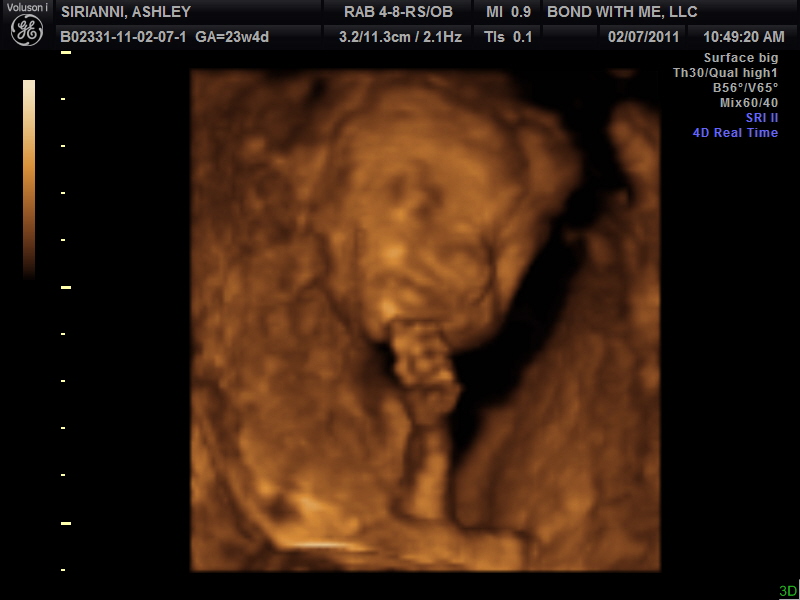

3D/4D

Ian and I will be celebrating 5 years of marriage on Friday, February 11th!!! For our anniversary he surprised me and took me for a 3D/4D ultrasound. It was so neat!! If you are pregnant I totally recommend this. It is pretty pricey, but I feel like it was worth every penny. They gave a bunch of black/white printed pictures and a c.d. with all of the pictures on it and then they will be mailing us a DVD of the babe plus a color photo collage! I can't wait to get the DVD!

I am so in love with this babe! It was amazing to peek inside at our little one! The baby yawned like 5 times. I guess this little one takes after it's momma already! He/she opened it's eyes for us, was playing with the umbilical cord and just looked so cozy! I know I have said it before, but this babe is sooo active!! It is constantly moving and I am even starting to be able to feel movement when I am up and moving around which a new thing. I also, was at the midwife yesterday and I gained wayyyyy too much weight in one month! Oh well, I keep saying as long as this baby gets big and fat I don't care how much weight I gain! Everything else checked out perfect!! I can't believe how quickly this pregnancy is flying by! Only 114 more days or sooner and the babe will be here! I am sure CHOP will want this baby out as soon as it is considered full term.